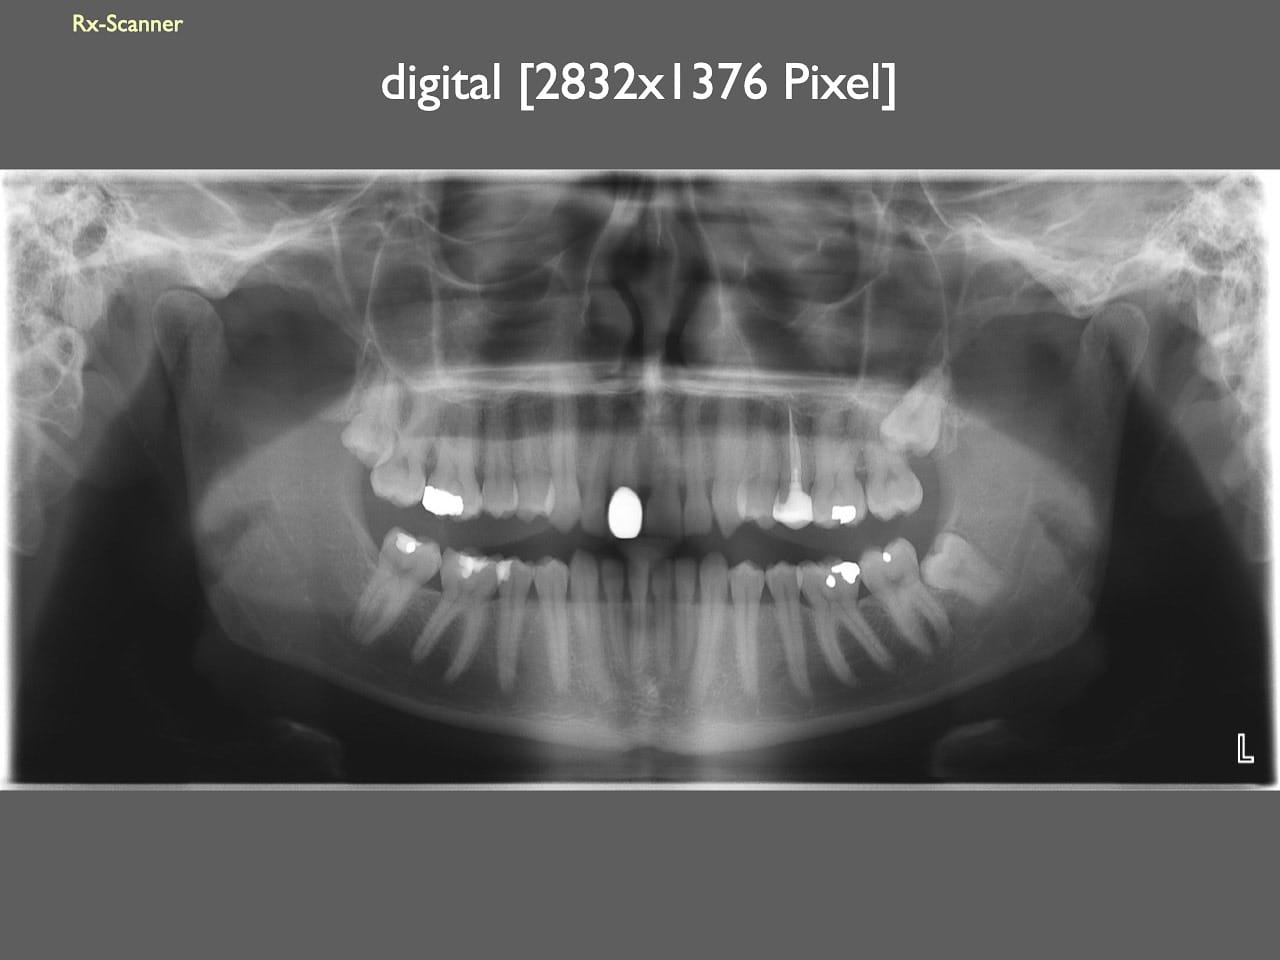

dental Scannen in der Zahnarztpraxis. Study Club vom 28.2.2010. Von peter portmann, Veröffentlicht am 28. Feb. 2010 — 3 min Lesezeit dokumentationfoto Auf dieser Seite Zahnarztpraxis-Trilogie zu Fotografie und Dokumentation Portrait Fotografie Scannen Scannen